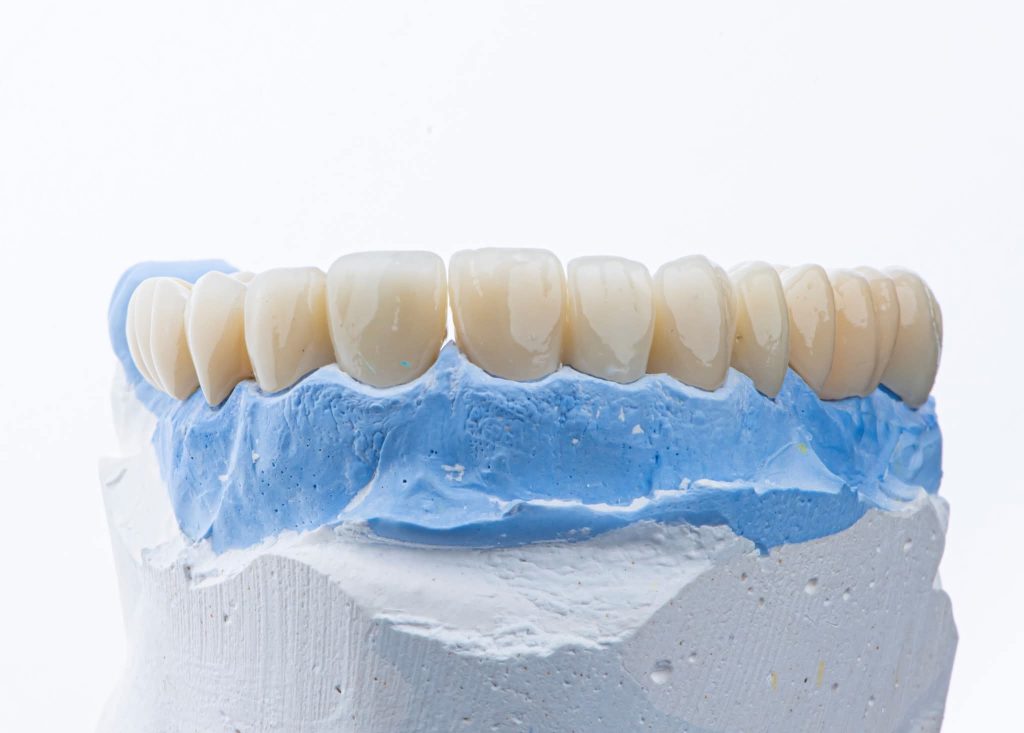

The case was transferred to a semi-adjustable articulator, where the vertical dimension was increased by 5 mm. A diagnostic wax-up and removable prostheses were created at the new vertical dimension, guided by the curve of Spee using Broadrick’s Occlusal Plane Analyzer. Silicone indices were fabricated for both arches.

3. Definitive Phase:

This phase began with the upper arch:

Preparation of teeth and insertion of the fixed prosthesis.